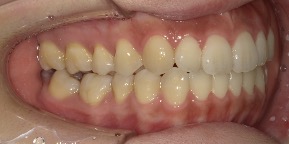

33歳女性のビフォーアフター

| 診断 | 空隙 |

| 治療方針 | 治療方針:前歯の咬合関係改善と空隙閉鎖を主な目的にて主にIPR(歯と歯の間をわずかに削合してスペースを獲得する方法)を組み込んだ動的矯正治療を行い、空隙、前歯咬合を改善後、保定を行う。臼歯部の咬合関係はプランの都合上維持することとした。 |

| 治療費 ※ | 67万8千円(診断、型取り、矯正中のメンテナンス、保定装置を含む料金) |

| 治療期間 | 6か月 |

| リスク | 1日20時間以上マウスピースを使用できない場合、歯が動かなかったり、想定しない誤差により不完全に終わる可能性がある。装着時や食事時に痛みを伴う。歯肉退縮や虫歯になるおそれがある。また、指導通りに装着できていない場合や適切なブラッシングが出来ていないとそのリスクが高くなる。歯根が短くなることがある。ごくまれに歯の神経が損傷してしまうことがある。過去にぶつけたり深い虫歯治療をしたことがあるとそのリスクはやや高くなる。矯正後には保定装置が必要。適切な使用ができない場合、後戻りの原因となる。将来的に歯並びが動いて再矯正が必要な場合がある。親知らずが正常に生えていない場合、その可能性がやや高くなる。 |